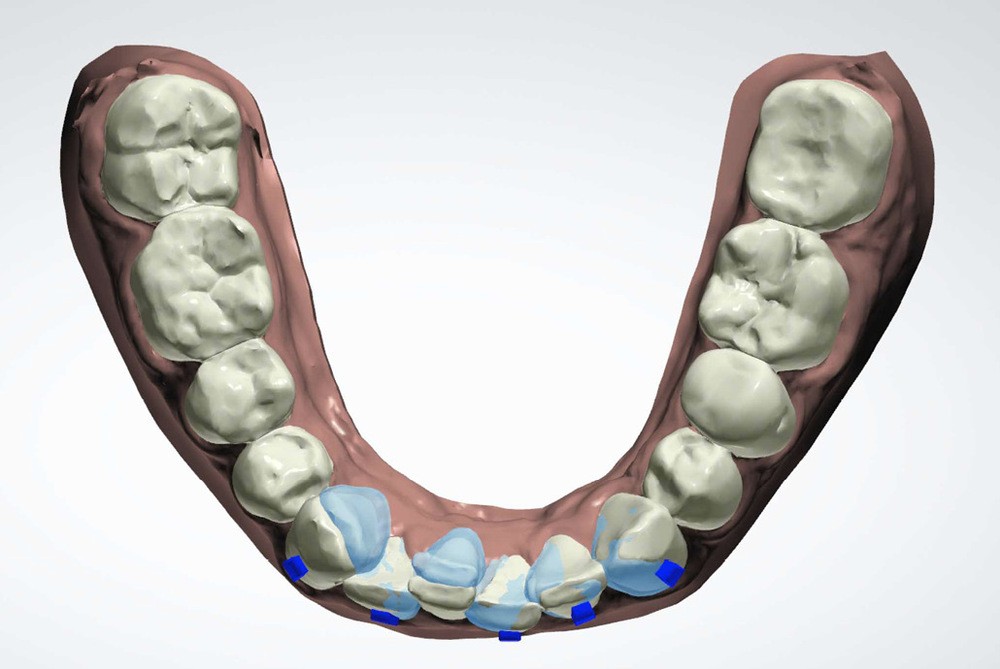

Plan de traitement

(fig. 4 à 10)

Le plan de traitement établi conjointement avec son chirurgien-dentiste traitant consiste à réaliser un alignement dentaire mandibulaire et à réaliser des extractions de 16 et 15 pour un remplacement par prothèse implanto-portée.

Le gain de place se fera par des réductions interproximales sur la zone incisivo-canine mandibulaire.

Il est décidé de ne pas redresser la 43 complètement afin de ne pas entraîner d’interférences occlusales.

Un accompagnement par des meulages occlusaux est réalisé.